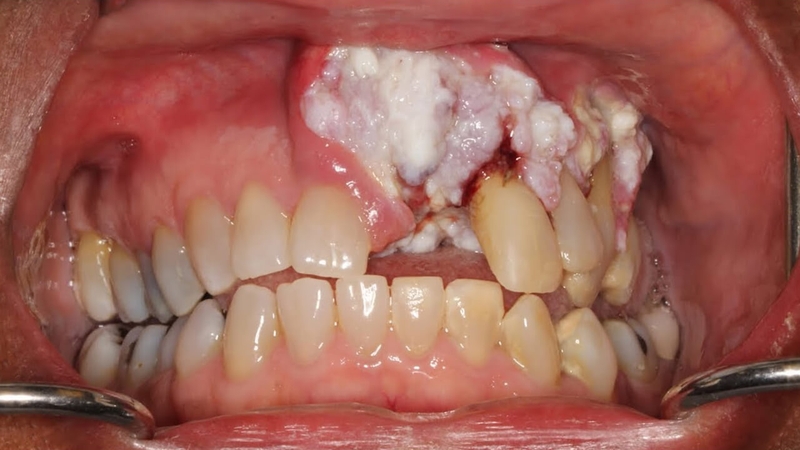

Ung thư nướu răng thuộc nhóm các bệnh ung thư khoang miệng, trong đó tế bào ung thư hình thành và phát triển ngay trên bề mặt nướu. Khối u có thể xâm lấn các mô xung quanh và di căn tới các cơ quan lân cận hoặc cơ quan ở xa theo đường bạch huyết, hay còn gọi là khối u ác tính.

Ung thư nướu răng xảy ra khi các tế bào nướu răng phân chia liên tục, mất kiểm soát với tốc độ nhanh, từ đó hình thành khối u.

/https://cms-prod.s3-sgn09.fptcloud.com/cach_dieu_tri_ung_thu_nuou_rang_1_94d0219c3b.jpg) Ung thư nướu răng là bệnh lý nguy hiểm với tỷ lệ tử vong cao

Ung thư nướu răng là bệnh lý nguy hiểm với tỷ lệ tử vong caoNguyên nhân của sự mất kiểm soát này vẫn chưa được biết rõ. Tuy nhiên, nhiều nghiên cứu đã chỉ ra các yếu tố nguy cơ gây bệnh như:

Ở giai đoạn này, bệnh rất khó phát hiện vì người bệnh sẽ có biểu hiện giống như nhiệt miệng, viêm lợi. Trên niêm mạc miệng của bệnh nhân sẽ xuất hiện các vết loét có màu đỏ hoặc trắng, gây đau đớn và chảy máu. Vết loét lâu lành hơn bình thường, có thể kéo dài trên 2 tuần, kèm theo đó là sự thay đổi màu sắc của vùng niêm mạc xung quanh.